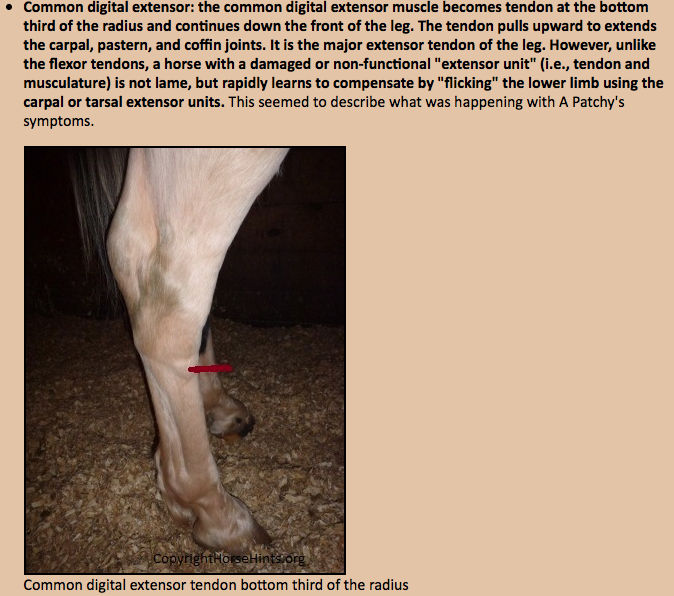

HORSE SENSE: The lowdown on lower limb injuries 04 August 2017 Premium